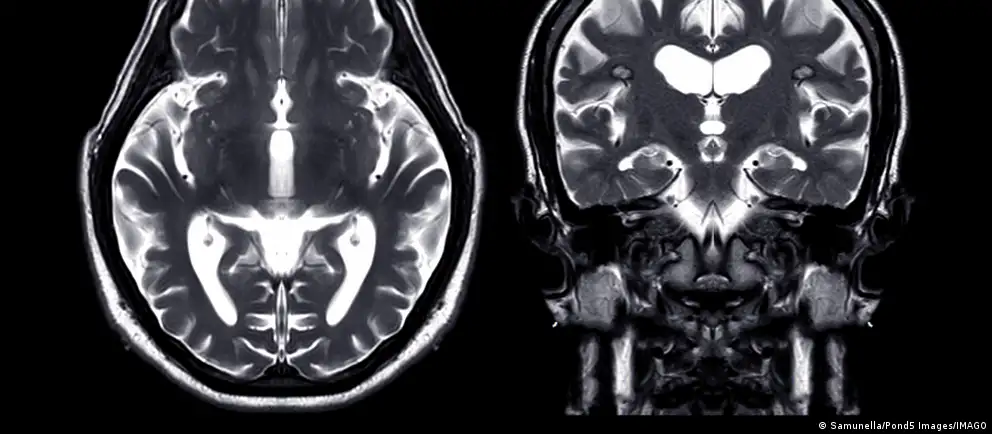

حدوث نزيف في الدماغ، حيث يُحتمل أن يكون النزيف قد ساهم في الخرفصورة من: Samunella/Pond5 Images/IMAGO

وفقًا لموقع "أخبار علوم الأعصاب" (Neuroscience News)، اكتشف العلماء من خلال دراسة بيانات 15 ألف مريض زيادة في حالات الخرف بعد حوالي 5.6 سنوات من حدوث نزيف في الدماغ، حيث يُحتمل أن يكون النزيف قد ساهم في الخرف نتيجة لتراكم مادة بيتا أميلويد أو تلف الأوعية الدموية. بناءً على هذه النتائج، يوصي الباحثون بضرورة إجراء فحوصات عقلية منتظمة للمرضى الذين تعرضوا للنزيف.

قال الدكتور صمويل بروس الباحث الأول في الدراسة، إن النزيف الدماغي يزيد بشكل واضح من خطر الإصابة بالخرف، بغض النظر عن نوعه. وبناءً على ذلك، هذا يعني أن الأشخاص الذين تعرضوا لنزيف دماغي يجب أن يخضعوا لفحوصات منتظمة لفحص وظائفهم الإدراكية، إذ إن ذلك قد يساعد في اتخاذ قرارات بشأن رعايتهم المستقبلية.

من خلال استخدام بيانات التأمين من برنامج ميديكير بين عامي 2008 و2018، درس الدكتور بروس وزملاؤه حالة حوالي 15,000 شخص تعرضوا لأنواع مختلفة من النزيف الدماغي. على الرغم من أن النزيف قد يحدث بسببإصابات في الرأس، إلا أنهم ركزوا على الحالات التي تحدث بشكل عفوي.

وقد وجدوا أن هؤلاء المرضى كانوا أكثر عرضة للإصابة بالخرف بعد حوالي 5.6 سنوات من النزيف مقارنة بأكثر من مليوني شخص لم يتعرضوا لنزيف.

وفقًا لدراسة أجراها باحثو جامعة ويل كورنيل، شملت مجموعة كبيرة من كبار السن في الولايات المتحدة، تبين أن النزيف داخل الجمجمة يضاعف خطر الإصابة بالخرف. وقد لوحظ هذا الخطر بشكل مستمر عبر مختلف أنواع النزيف داخل الجمجمة.